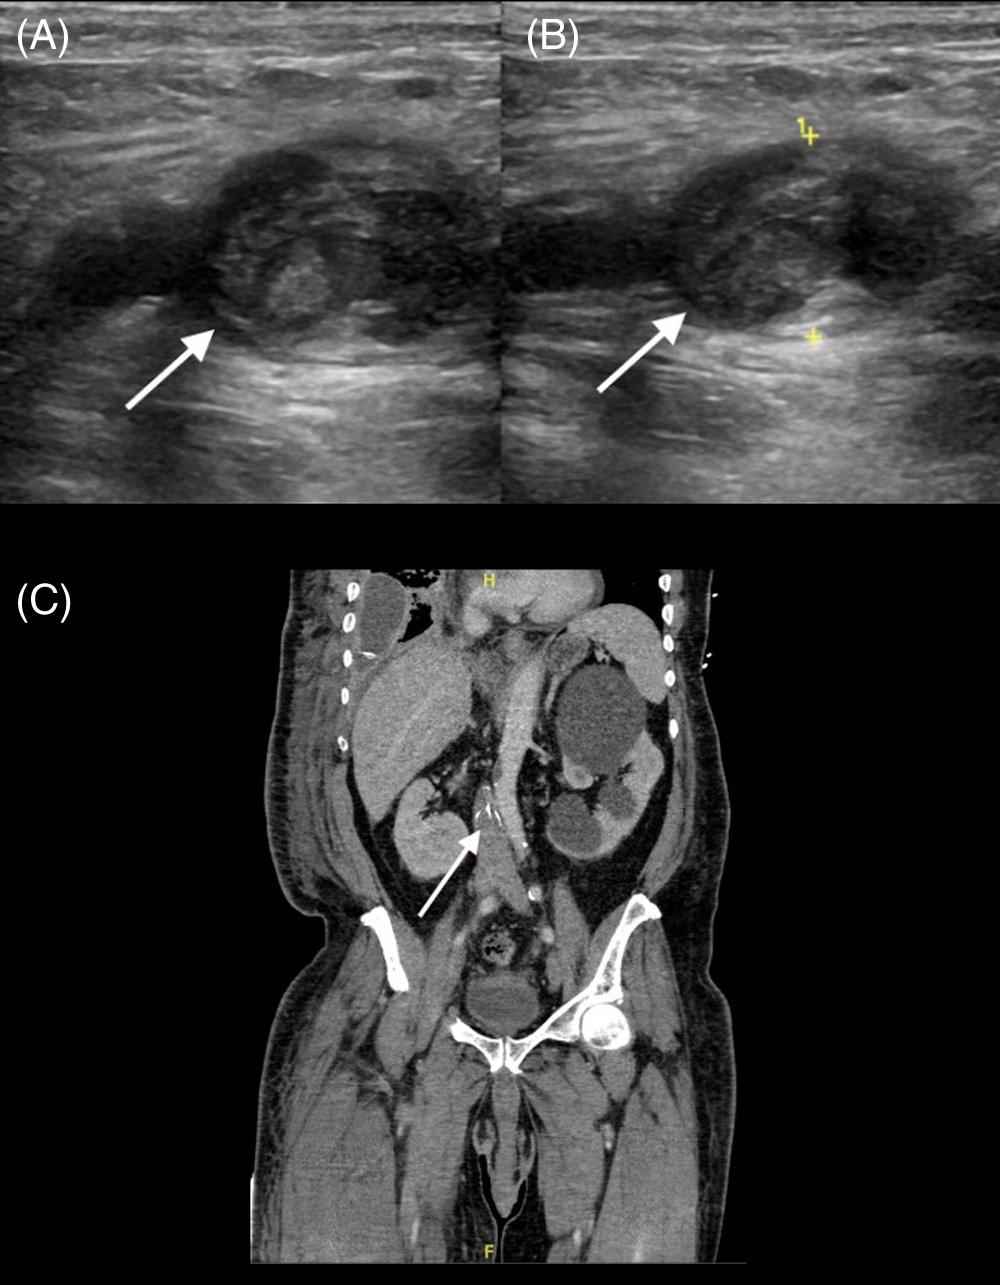

Image. Computedtomographyabdomenwithintravenouscontrast demonstratingdilated, fluid-filledloopsofsmallbowelandapattern ofswirlingmesentericvesselscalledthewhirlpoolsign(arrow).

Onpresentationthepatientwasinnoacutedistressbut wasclammyandtachycardicatarateof118beatsper minute.Onexam,herabdomenwasdiffuselytenderwithout distentionorperitonealsigns.Shehadanelevatedwhite bloodcellcountat17 × 103 permicroliter(K/μL)(reference range4.5–11.0K/μL),anINRof5.5,andalacticacidof 3.7millimolesperliter(mmol/L)(0.4–2.0mmol/L).An abdomenandpelvisCTwithintravenous(IV)contrast showed findingssuspiciousforclosedloop,smallbowel obstruction.TheCTalsodemonstratedevidenceofswirling ofthemesentericroot,knownasawhirlpoolsign(Image, Video).The findingsofthewhirlpoolsignonCTsuggested mesentericvolvulusasthecauseofherbowelobstructionand promptedemergentsurgicalconsultation.

pathology.However,radiographsareofteninconclusivein midgutvolvulusbecauseevenapositive “doublebubble” signindicatingasmallbowelobstructiondoesnotruleouta concomitantmidgutvolvulus.7 Computedtomographywith IVcontrastgivesmuchgreaterdetailoftheabdomenandcan provideevidencesuggestiveofamidgutvolvulus.ClassicCT imaging findingsincludeawhirlpoolsignoftwisted mesentery,malrotatedbowelconfiguration,inverted superiormesentericarteryandsuperiormesentericvein relationship,bowelobstruction,andfree fluid/freegasin advancedcases.8 ThewhirlpoolsignseenonCTrepresents themesenteryandsuperiormesentericveinwrapping aroundthesuperiormesentericarteryina counterclockwisedirection.